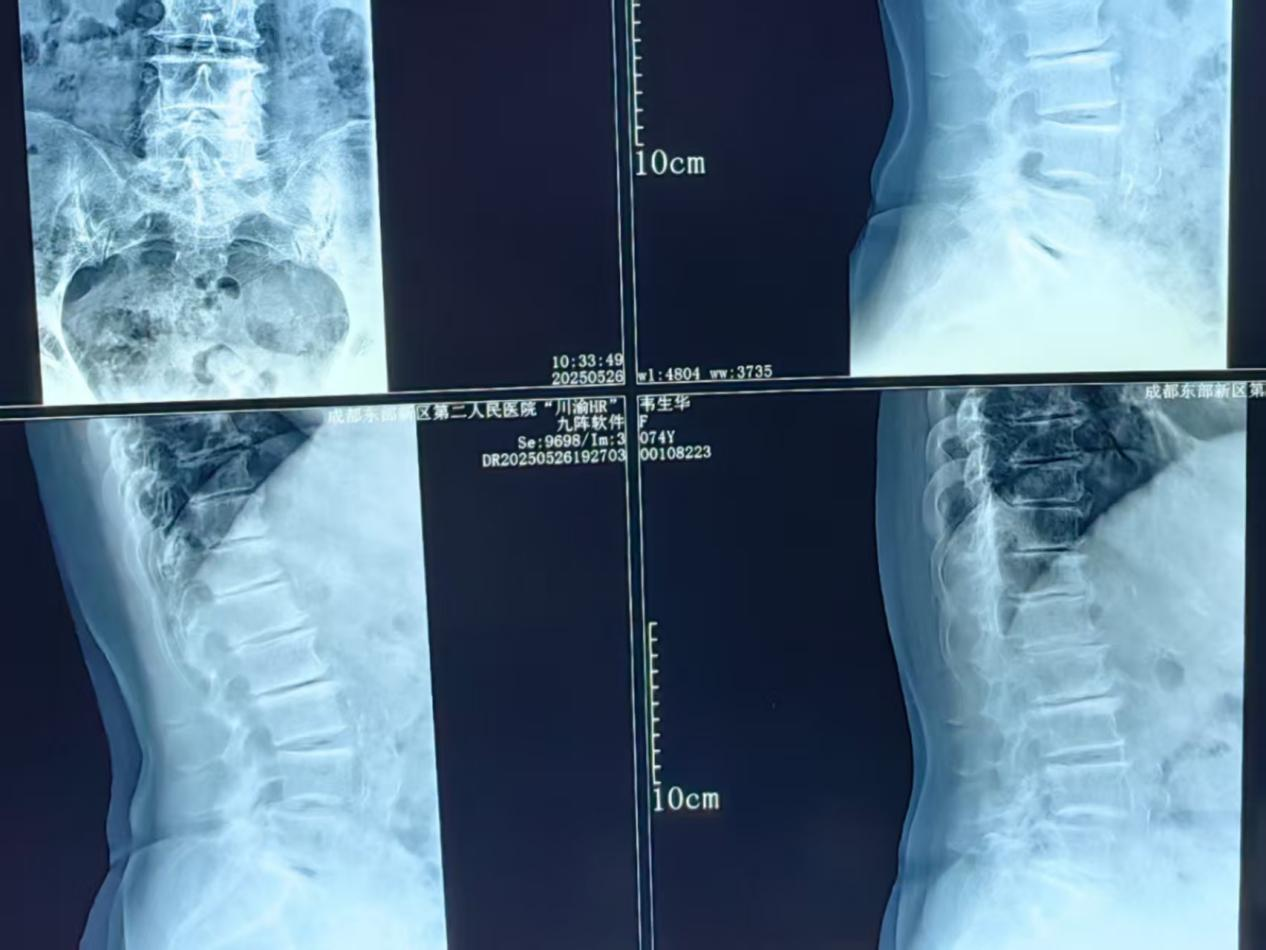

术中医生操作画面及患者术后DR片,椎体滑脱完全纠正,重建脊柱序列性及稳定性